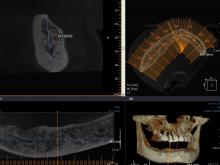

事前にCTを用いて埋入するインプラントの大きさや深さを確認してから手術を行いました。

本日は、右下23相当部に二本です。

術後の確認のパノラマで確認。

バッチリですね。